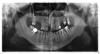

altombo Опубликовано 26 января, 2010 Автор Поделиться Опубликовано 26 января, 2010 Более четкий снимок. Интересует, нужно ли ставить имплантант на место верхней левой 5,6 левый верхний уже удален, если ставится мост между 4 и 7. Можно ли обойтись без моста, а просто внедрить имплантанты вместо 5,6 зубов. Ссылка на комментарий

Doc Опубликовано 26 января, 2010 Поделиться Опубликовано 26 января, 2010 Более четкий снимок. Интересует, нужно ли ставить имплантант на место верхней левой 5,6 левый верхний уже удален, если ставится мост между 4 и 7. Можно ли обойтись без моста, а просто внедрить имплантанты вместо 5,6 зубов. В данном случае оба зуба под мостом мертвые, а потому нуждаются в протезировании в любом случае. Другой вопрос, что установка имплантатов и изготовление независимых коронок, а не цельного моста - все равно грамотнее, чем мост. Но в принципе, если стоит вопрос в цене, умении и желании доктора ставить имплантаты или по какой другой причине не хочется ставить имплантаты, то можно обойтись и мостом. Ставили раньше мосты и стояли многие годами. Ссылка на комментарий

Bier Опубликовано 27 января, 2010 Поделиться Опубликовано 27 января, 2010 Уважаемые господа, не могли бы вы проконсультировать (по снимку) по паре вопросов:1. Каким образом правельнее установить имплантанты на левую верхнюю челюсть 5,6 зуб. Мне предложили поставить мост между 4 и 7, а также для укрепления сделать имплантант на 5. 6 удалить. вот это категорически нельзя делать. Либо просто мост 4-7, либо два имплантата 5,6. Ссылка на комментарий

annda Опубликовано 27 января, 2010 Поделиться Опубликовано 27 января, 2010 вот это категорически нельзя делать. Либо просто мост 4-7, либо два имплантата 5,6.Длинноват мост-то...Лучше имплантаты Ссылка на комментарий